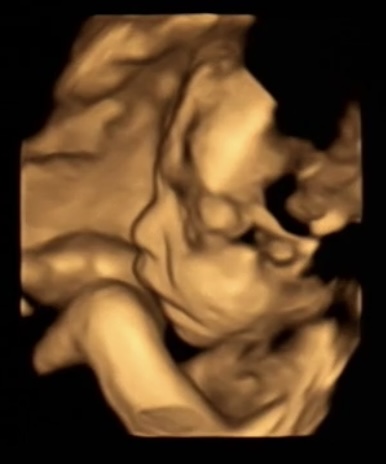

赤ちゃんの顔@4D

今日の検診ではいつものエコーに加えて

4Dで赤ちゃんのお顔を見させてくれました。

おおー

なるほど、人間のお顔をしておる。